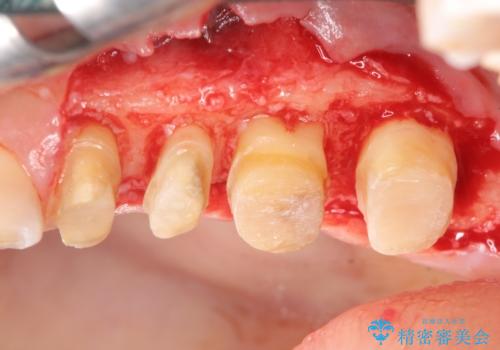

虫歯の深化により根管治療、歯周外科手術を行い歯肉の状態を改善し精密なセラミッククラウンを製作する治療を計画します。

セラミック治療の長期的な予後を見込むために、根管治療、歯周外科を行いクラウン装着前の環境を整えておくことが肝要です。